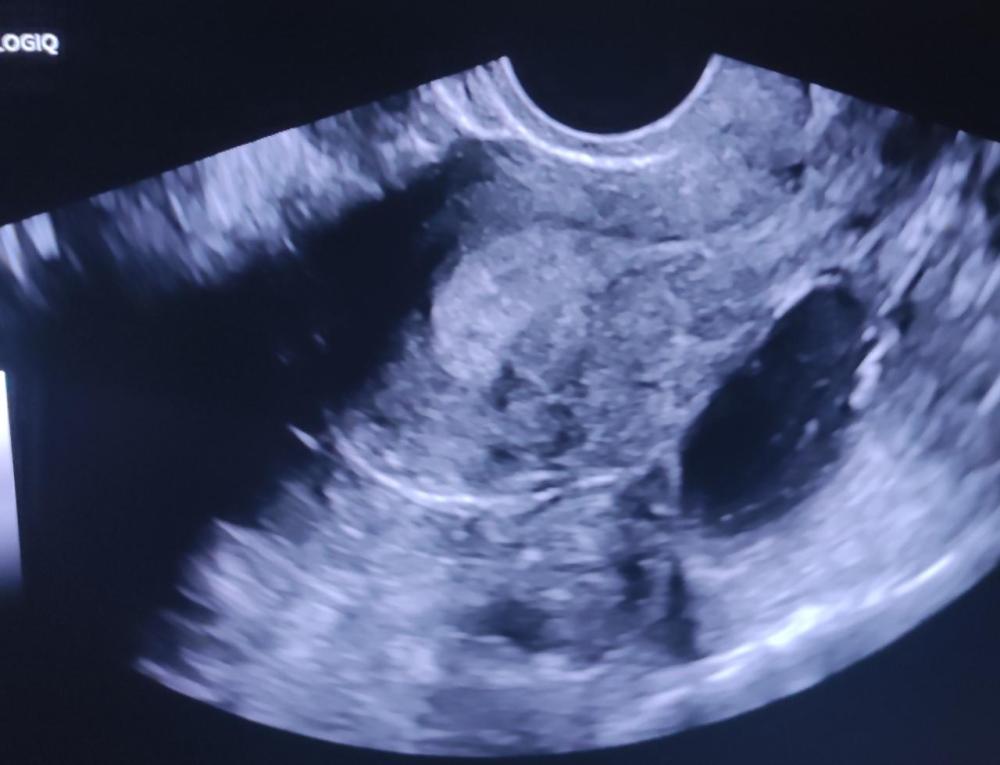

Σου στέλνω φώτο πως φαινόταν σε μένα. Δυστυχως τώρα που έψαξα και το χαρτί, βλέπω ότι δε σημείωσε η γιατρός πόσα εκατοστά ήταν 🤔 Ελπίζω για το καλύτερο, ειλικρινά 🙏 -

Χμμ όντως πολύ περίεργα μας τα λέει ο γιατρός! Αλλά να σου πω τη δική μου εμπειρία, εγώ είχα κάνει υπέρηχο πέρυσι τον Ιανουάριο στα πλαίσια του ετήσιου τσεκ-απ, και ήμουν έγκυος αλλά δε το ήξερα ακόμα, 28η μέρα του κύκλου, 3-4 μέρες πριν την αναμενόμενη περίοδο. Τότε η γιατρός που μου έκανε τον υπέρηχο είχε δει κάτι στρογγυλό (που τελικά ήταν ο σάκος όπως αποδείχτηκε αργότερα) το οποίο μου το εξήγησε ότι δεν ήταν κύστη, ούτε κάποια παθογένεια, αλλά δε μπορούσε να προσδιορίσει με ακρίβεια. Και τότε μου είπε ότι δεν έπρεπε να έρθω για τον υπέρηχο στο τέλος του κύκλου γιατί ειναι παχύ το ενδομήτριο και δεν υπάρχει καλή ευκρίνεια στο τι ειναι το καθετί - κι ότι θα ήταν καλύτερο να πηγαινα μετά την περιόδο και πριν την ωορρηξία. Τέλος πάντων, μετά από μια εβδομάδα που μου είχε καθυστερήσει κι η περιόδος έμαθα ότι είμαι έγκυος, οπότε ποτέ δε ξέρεις 🤞 όπως και να χει κάνε μια χοριακή να είσαι σίγουρη αλλιώς βουρ για τεστάκια ωορρηξίας και πάμε για τον επόμενο κύκλο! -